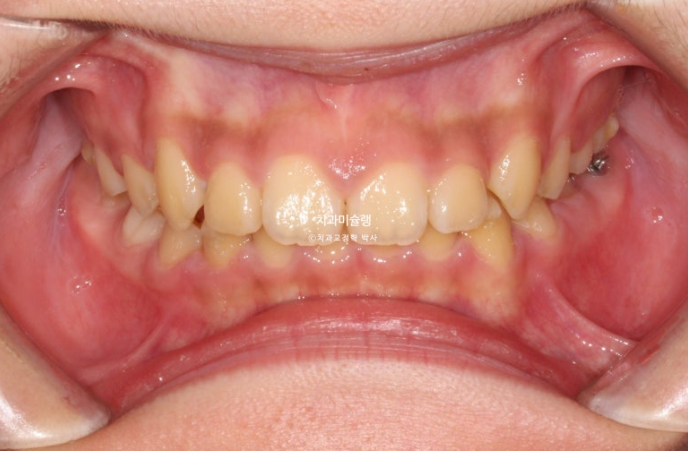

24.04

과개교합의 개선

배열의 개선

이제 막 남아있던 유치들이 빠지고 영구치가 나오는 시기라 전략적으로 쉬는시간을 갖습니다.

21번 장치를 잘때만 끼면서 영구치 맹출을 기다리는 시간이죠.

24년 10월까지 6개월간 남은 영구치 맹출을 기다립니다.